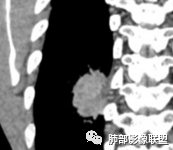

甄德强老师分析

多发小灶性坏死。强化程度轻,几乎观察不到完整血管影。

浅分叶,边界清

近端支气管堵塞

肺气肿背景

综上考虑鳞癌,鉴别低分化腺癌